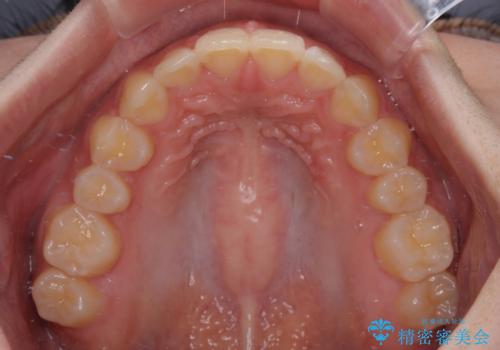

前歯のすきっ歯を治したい インビザラインによる矯正治療

一度インビザラインのマウスピースセットをお渡しすると1年以上来院されず、マウスピースを破損したり紛失したりすると来院されるというのんびりとしたペースで治療を行ったため、4年間という長期にわたる治療となりました。

最終的には隙間は全て閉じ、綺麗な仕上がりとなりました。